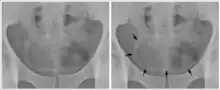

La calcification de la paroi de la vessie sur une radiographie du bassin, chez un homme subsaharien de 44 ans. Ceci est dû à une schistosomiase urinaire.